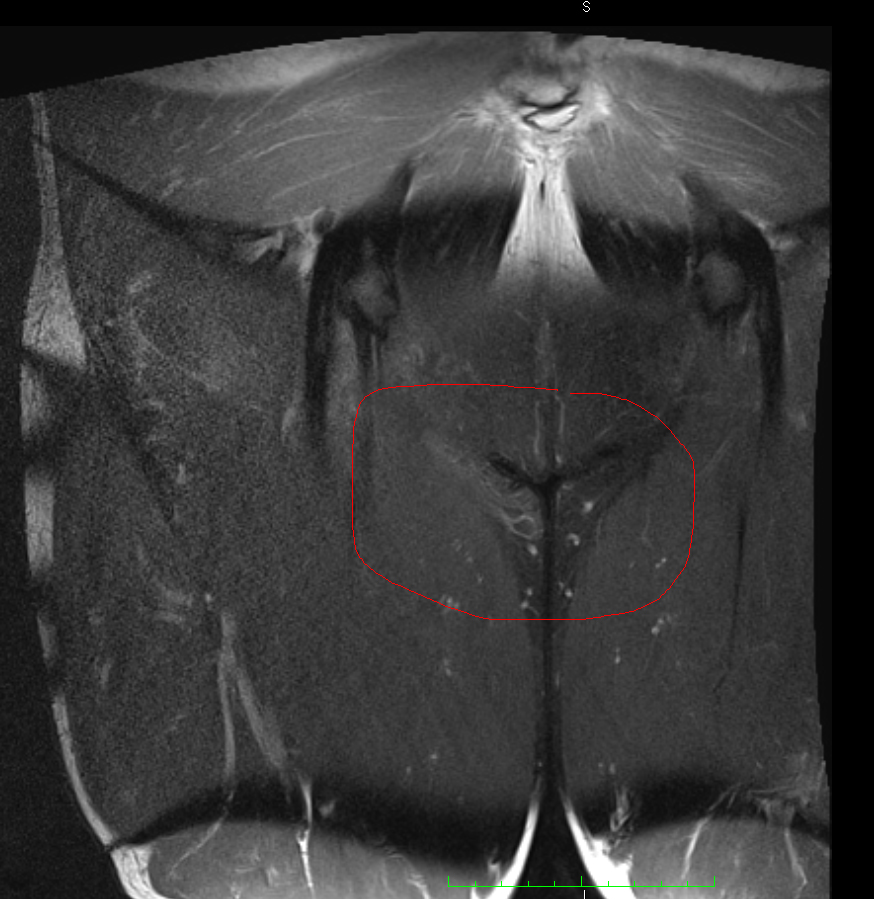

Nun habe ich mir die MRT-Bilder selber angeschaut und bin der festen Meinung, dass genau in dem Bereich wo ich Probleme habe, eine deutliche Auffälligkeit im Vergleich zum anderen Bein zu sehen ist. Diese hellere Struktur ist wohlgemerkt nicht nur in einer Schicht der Aufnahme zu sehen, sondern auf 14.

Kennt sich jemand mit MRT-Bildern aus und kann dazu was sagen? Ist dort eine Auffälligkeit zu sehen, oder ist das Zufall? Deutet dies auf eine Entzündung hin? (Ja ich gehe noch zum Arzt mit den Bildern)

Anbei einmal zwei Unterschiedliche Sequenzen. Das schwarze Y was ihr seht ist der Bereich linkes Bein/rechtes Bein, oben Genitalbereich. Links ist eine deutliche hellere Struktur zu erkennen als rechts (Adduktoren).